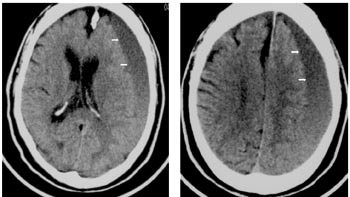

Pasienten ble overflyttet til regionsykehus, der det neste dag ble foretatt evakuering av kronisk subduralt hematom. Det ble anlagt to borehull, og i begge tømte det seg væske under høyt trykk. Forløpet var ukomplisert, pasienten var oppegående og kjekk og ble utskrevet til hjemmet fem døgn postoperativt med beskjed om ikke å ta acetylsalisylsyre de neste to ukene. Ti døgn senere (15 døgn postoperativt) ble han reinnlagt. Han klaget igjen over at høyre hånd ikke lystret ham, og fastlegen mente dessuten at han var mentalt tregere enn vanlig. Komparentopplysninger fra hans samboer indikerte at han hadde vært betydelig bedre kort etter operasjonen, men så var blitt dårligere. Ved undersøkelsen kunne man få inntrykk av en noe redusert nærhukommelse. Han lette etter ordene, og det var tydelig temporeduksjon i høyre sides arm og bein samt klossethet for finere fingerbevegelser på høyre side. Videre ble det bemerket lett redusert sensibilitet og noe livligere dype senereflekser på høyre side. Ny cerebral CT-undersøkelse (fig 2) viste en venstresidig subdural effusjon av nærmest uendret størrelse, men det var nå oppstått ulik røntgentetthet (sjiktning) i væsken som uttrykk for mulig reblødning.

Om lag to uker etter den andre operasjonen fortalte imidlertid samboeren om økende nattlig uro og forvirring. Han stod opp flere ganger om natten og falt. Han ble derfor reinnlagt i døgnpost, og hadde nå klart mer uttalte pareser i høyre bein, som han ikke klarte å løfte mot tyngdekraften. Han ble dessuten beskrevet som tydelig hukommelsessvekket. Ny cerebral CT-undersøkelse viste et venstresidig subduralt hematom av nærmest uendret størrelse med forskyvning av midtlinjen mot høyre. Det ble på ny tatt kontakt med regionsykehusets nevrokirurgiske avdeling, men man mente der at det ikke var aktuelt å operere ham igjen.

I løpet av de neste dagene falt han flere ganger, var tung å få opp, og var periodevis tydelig forvirret. Det ble gjort ytterligere en CT-undersøkelse 24 døgn etter den andre operasjonen. Bildet var nærmest identisk med det som var tatt før den andre operasjonen (fig 2), og viste fremdeles et stort subduralt hematom med sjiktning og overskyting av midtlinjestrukturer. Det ble igjen tatt kontakt med nevrokirurgisk avdeling, som opprettholdt vurderingen av at ny operasjon ikke var indisert. Etter ytterligere fire døgn kom det imidlertid kontrabeskjed. For tredje gang ble det utført evakuering av kronisk subduralt hematom, sju uker etter den første operasjonen og fire uker etter den andre.

Uro og forvirring hos gamle pasienter blir ofte tolket som uttrykk for aldersdemens eller feiltolket som normale aldersforandringer. Symptomene hos vår pasient var imidlertid oppstått i løpet av kort tid, og de fluktuerte i løpet av døgnet. Dette er ikke typisk for demens, men derimot for delirium (tidligere ofte kalt akutt forvirring) (2, 3). Delirium har nesten alltid en underliggende somatisk årsak som kan behandles. De vanligste årsakene er infeksiøse, kardiovaskulære og cerebrovaskulære sykdommer samt legemiddelbivirkninger (4), men nær sagt alle akutte somatiske tilstander, også subduralt hematom, kan forårsake delirium. Hos vår pasient var det en dramatisk forverring av symptomene, mens endringene i CT-bildene var marginale. Det er et problem at valg av terapi i mange tilfeller baseres på radiologiske og andre supplerende undersøkelser, mens pasientens kliniske og funksjonelle tilstand vektlegges for lite. Retrospektivt kan vi se at tredje gangs evakuering av subduralt hematom trolig burde vært foretatt om lag to uker tidligere. Det kan ha medvirket til forsinkelsen at pasientens mentale og motoriske funksjonstap ikke ble kommunisert tydelig nok til regionsykehuset.